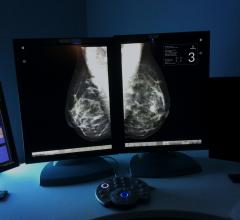

Annual breast cancer screening is a chapter many women are hesitant to add to their personal medical history books. Undergoing frequent mammograms and other imaging exams means growing that mid-life medical history, often in a complicated way. In breast health, access to prior exams is critical in determining if and how the images have changed. Radiologists and other specialists — typically at separate locations — require access to a detailed patient history in providing optimal, safe care. Patients, too, must be proactive about their own screening and care decisions, especially considering risks of radiation dose and other clinical treatments.

Despite decades of progress in breast imaging, one challenge continues to test even the most skilled radiologists ...